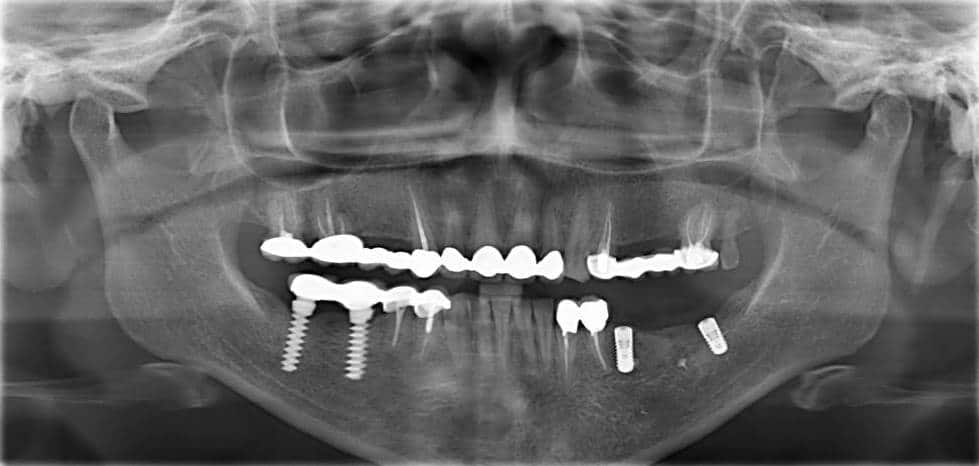

Initial radiographic situation

Radiographic evaluation after implant placement

Final radiographic evaluation